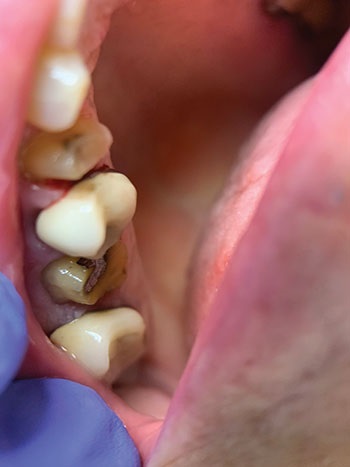

The extraction of tooth #13 was successful as its periodontal ligament was already compromised. Following the extraction, an FDA-cleared, non-toxic oral hydrogel wound dressing was applied at the extraction site. A hemostatic self-resorbing gauze was placed on top of the wound dressing to facilitate healing (Fig. 5).

Fig. 5: Tooth #13 extracted. Extraction socket protected with a non-toxic hydrogel wound dressing and hemostatic selfresorbing gauze.